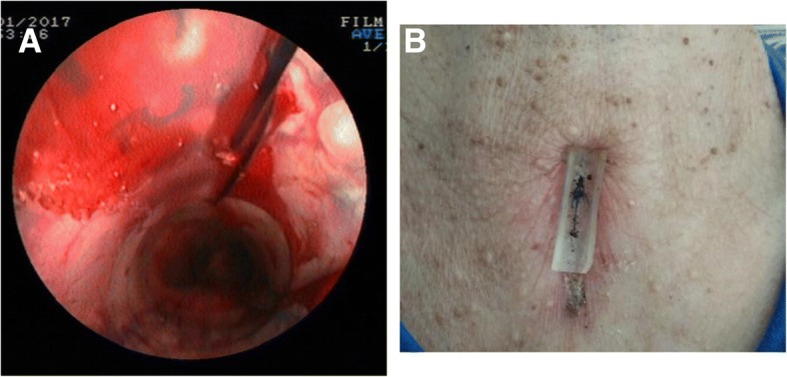

After general anesthesia, the patients were placed in trendelenburg position. A rigid bronchoscope was inserted into the trachea under the guidance of a flexible bronchoscope. Ventilation was assured by using a ventilator. After tracheal stenosis was treated with cryoresection, acusection, argon plasma coagulation, balloon dilatation properly, the membrane-covered metal stents (Micro-Tech Co. Ltd., Nanjing, China) or Dumon stent (Novatech, La Ciotat, France) were placed during a rigid bronchoscopy procedure. Under endoscope, a double-needle gastropexy device of PEG kit (Create Medic Co., Ltd., Yokohama, Japan) was applied. The puncture was performed at the part between the inferior margin of the cricoid cartilage and the suprasternal notch. After the position of stent was adjusted satisfactory, the anterior of the stent was fixed onto the antetheca of the trachea and its front tissue under endoscopic monitoring. To prevent surgical suture from cutting the skin, a silicon pad (width of 1–1.5 cm and length of 3-4 cm) was placed on the skin at the puncture site (Fig. 1). A suture fixation about 1–3 stitches were done. Postoperatively, phone call following-up was done every month to see if there’s any complication.

Fig. 1.

Images of the operation procedures. a: Suture fixation method for the tracheal stent. b: Postoperative CT showing the silicon pad on the skin at the puncture site (as the arrow indicates)